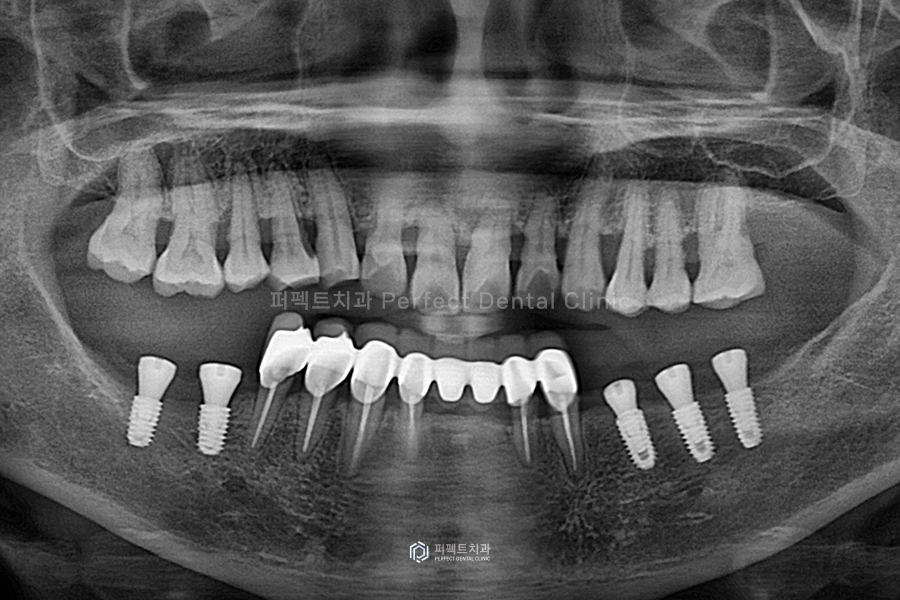

먼저 오른쪽 어금니 부분에 임플란트를 심고, 오른쪽 임플란트 식립, 그리고 앞니까지 다 심게 되었는데요.

교합 높이를 유지하는 것이 중요하기 때문에 어금니 부분에 즉시 임플란트를 식립하였습니다. 즉시 임플란트는 원데이 임플란트라고 말하기도 하는데요. 당일에 임플란트를 식립하고 임시치아까지 올리는 것을 말합니다. 이 환자분의 경우 교합 높이를 유지하기 위해 당일 임플란트를 식립하고 지대주 기둥을 제작, 임시치아를 제작하여 사용하도록 하였습니다.

아랫니 임플란트를 식립하는데에는 두 달 정도의 시간이 걸렸습니다.